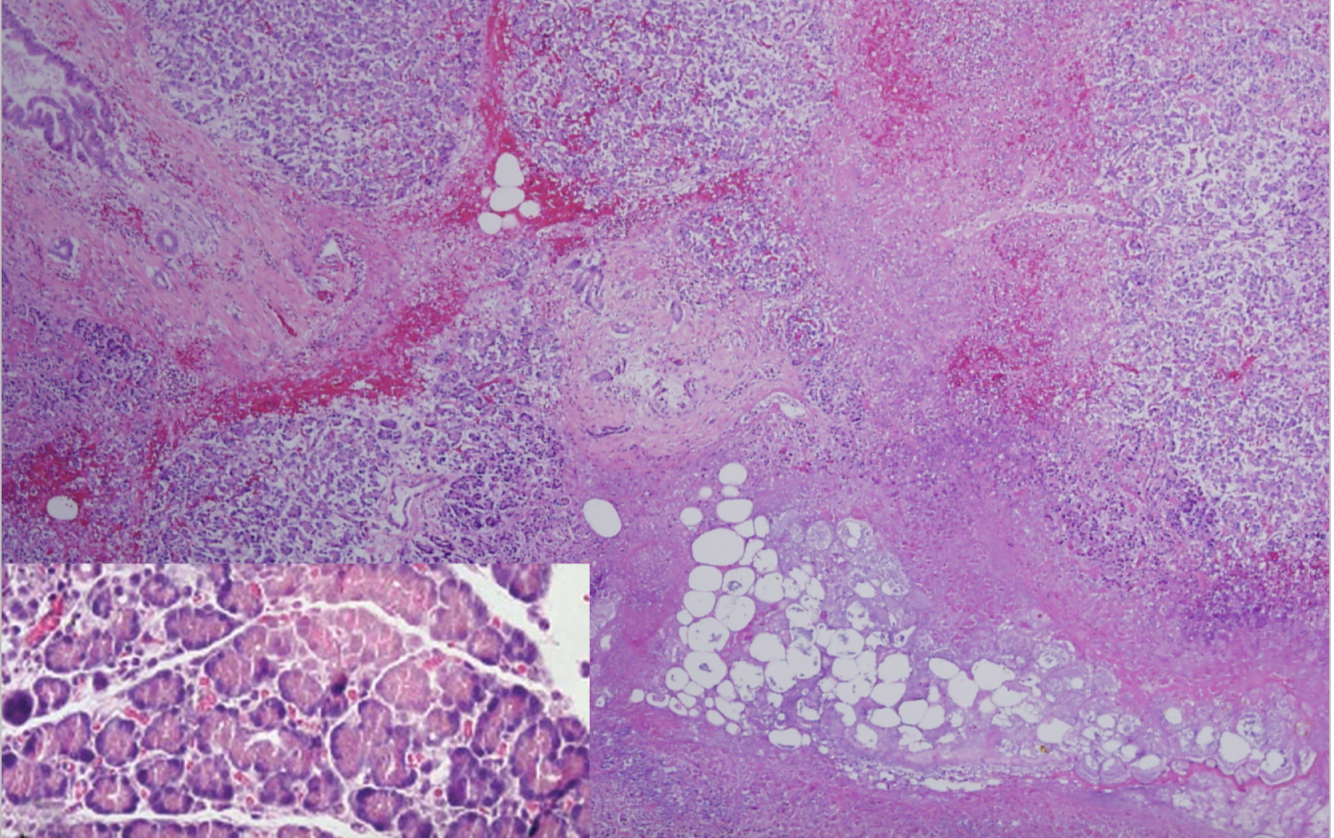

This is from the pancreas. What’s up wit it?

Fat necrosis and hemorrhage